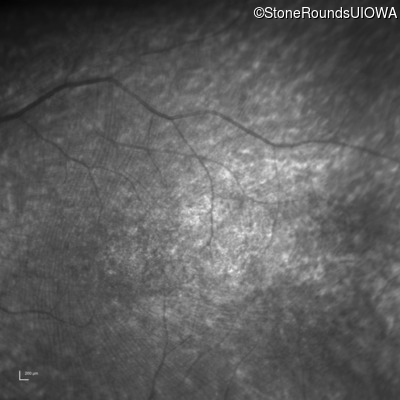

Age at visit: 7 years

This 7 year old boy's mother first noticed that he was tripping over objects in dim light about one year ago.

Diagnosis & molecular findings

Batten Disease PPT1 Thr75Pro ACC>CCC IVS6-1 G>T AR